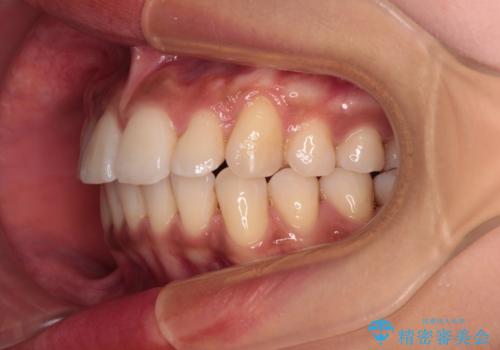

- 全体的な歯列の叢生を気にして来院された患者様です。

奥歯の咬み合わせを見ると、片方は上顎が下顎に対して相対的に前方にある状態でした。

咬み合わせを改善するためには、上顎臼歯を後方に移動させた咬み合わせにする必要があります。

インビザライン単体で改善することも可能ですが、ディープバイトのためインビザライン単体で達成する可能性が低いと考えられたため、カリエール・ディスタライザーという補助装置を併用して、より確実性を上げることとしました。

奥歯の咬み合わせ改善後に、インビザラインにて歯列を整えることとしました。